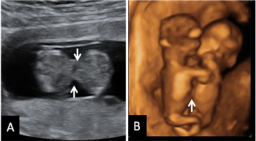

Trillizos de 9 semanas

La imagen de esta ecografía en 4D de este embarazo muestra tres fetos, uno de ellos independiente, que está "aislado" de sus dos hermanos gemelos. Ecografía 4D de trillizos de 9 semanas La ecografía en 4D no deja lugar a dudas: se trata de tres fetos, uno de ellos independiente (en la...